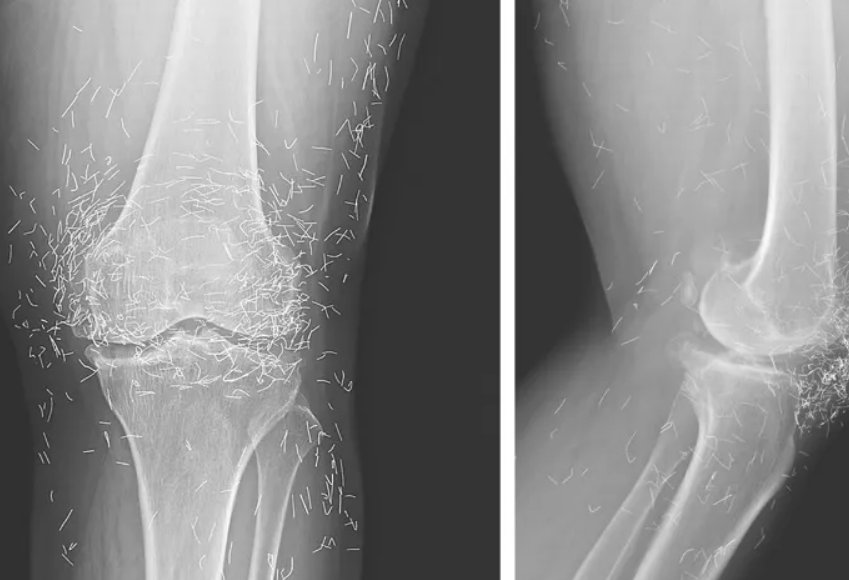

Al acudir nuevamente al hospital por dolor intenso, los médicos realizaron radiografías que mostraron engrosamiento y endurecimiento de la tibia, además de espolones óseos. Lo más sorprendente fueron cientos de diminutos hilos dorados incrustados alrededor de la articulación. La Mujer tenía “Hilos dorados” en las rodillas, insertados durante la acupuntura para estimular el tejido de forma continua.

Aunque estos hilos son visibles en radiografías, su presencia no está exenta de riesgos: pueden migrar, dañar tejidos cercanos o formar quistes. Este hallazgo subraya la importancia de conocer los antecedentes de tratamientos alternativos antes de realizar estudios de imagen.